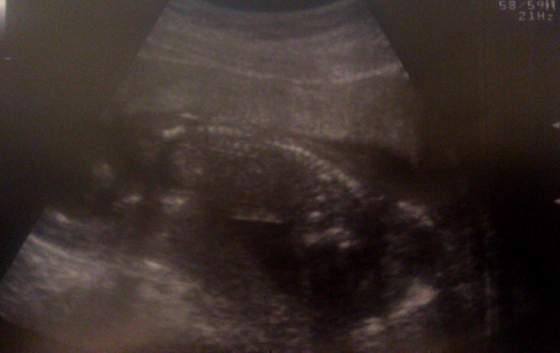

dzidzia zdrowa, ma już 10,2cm i waży 180g

Gin zrobiła bardzo dokładne USG, najpierw zaczęła dowcipnie,potem przeszła na brzuszne, pomierzyła wszystkie kości,obwody itp

Serce bije, jest prawidłowe 4komorowe, widać już żołądek i nerki, mózg prawidłowy, bez przepuklin itp itd.... Powiedziała że za 4tyg pomierzymy wszystko i posprawdzamy bardzo dokładnie, ale że już dziś bardzo dużo udało jej się zobaczyć i wszystko jest ok, więc ona jest spokojna i dobrej myśli

a co najważniejsze? BĘDZIE DZIEWCZYNKA!!!!

A tu foty: